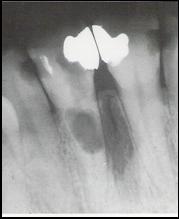

Radiologic - examenul radiologic trebuie sa indice o adaptare perfecta in ultimii 3-4mm apicali, iar varful conului sa fie localizat la aproximativ 1mm deasupra apexului radiologic;

Fig. 45 Adaptarea

conului principal de gutaperca a.scurt; b. foarte scurt; c. lungime corecta dar

prea ingust; d.lungime si

adaptare corecta